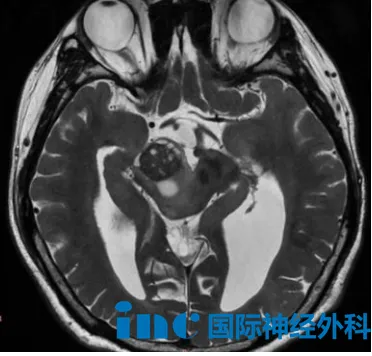

5岁女孩园园,于2025年4月因突发头晕、呕吐就诊,检查发现第三脑室和左侧丘脑存在病变。经“第三脑室底造瘘术+病损切除术”,术中切除了第三脑室内病灶,而左侧丘脑病灶因外观未见异常,未作处理。术后病理诊断为混合性胶质神经元肿瘤(WHOⅠ级),建议定期随访。2026年1月复查,第三脑室后部-左侧丘脑仍有异常信号,大小分别约为6×6mm、14×9mm。面对是否需再次手术、何时手术更为合适的问题,巴教授表示可以手术,观察的风险是肿瘤有可能进展。手术的目标当然是尽可能实现肿瘤全切除。但在实际操作中,我们必须根据术中情况审慎判断,在安全的前提下切除病灶——毕竟我们首要确保的是不造成患儿瘫痪或其他神经功能损伤。